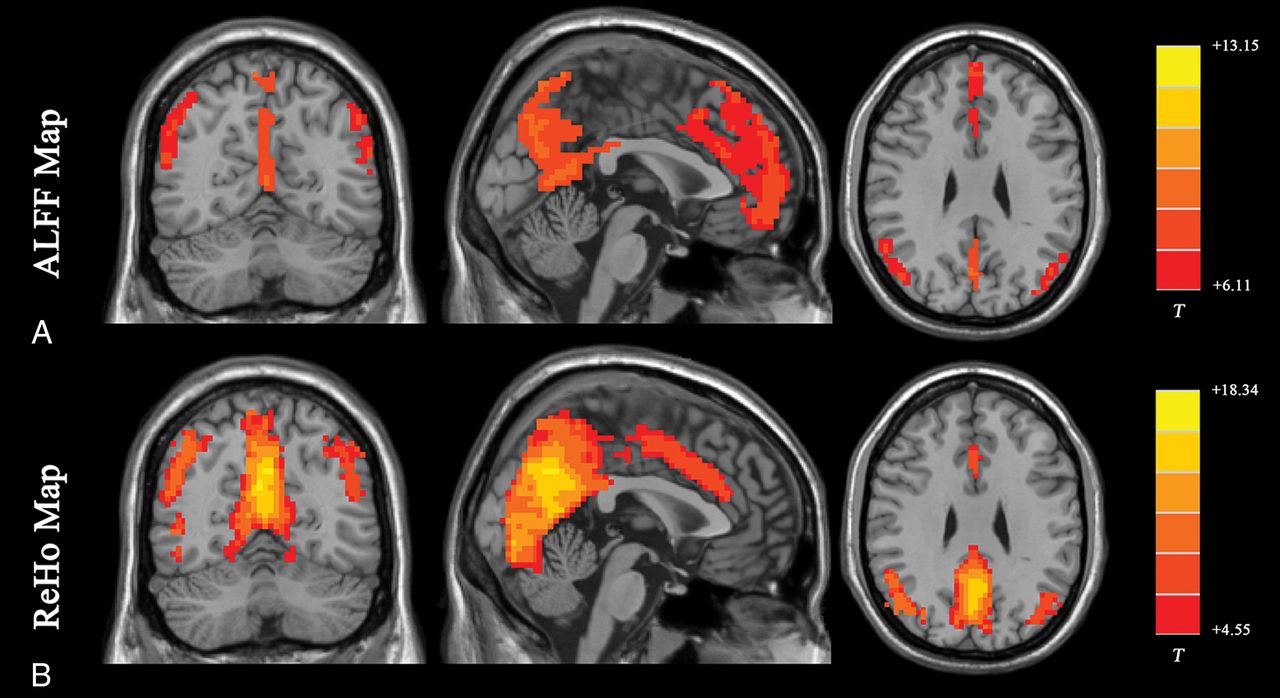

The ALFF method measures the total power of the BOLD signal within the low-frequency range between 0.01 and 0.1 Hz (Fig 1A35; the results are visualized with the REST Slice Viewer; http://www.restfmri.net36). ALFF is proportional to regional neural activity.35 Fractional-ALFF is a variant that measures the power within the low-frequency range (0.01–0.1 Hz) divided by the total power in the entire detectable frequency range and represents the relative contribution of the low-frequency oscillations.37 ALFF and fractional-ALFF measure regional brain activity only (like traffic in cities on a map, ALFF reveals the density of “traffic” as an absolute value, while fractional-ALFF looks at the density of traffic as a proportion in cities). Thus, they do not provide information on functional connectivity between brain regions.

Results of ALFF and ReHo studies (1-sample t test results of 200 healthy volunteers [M.W., unpublished data, February 6, 2017]). A, ALFF results. B, ReHo results. Results of increased ALFF and ReHo are mostly overlapped with the default mode network, which is activated at resting-state in healthy volunteers. (For different kinds of patients, abnormal ALFF or ReHo findings may be detected in other brain areas in the resting-state.) Both ALFF and ReHo results reflect regional neural activities. ALFF is focused on measuring the strength of the activity, while ReHo is more specific for coherence and centrality of regional activity. T indicates peak intensity.

ReHo analysis is a voxel-based measure of the similarity between the time-series of a given voxel and its nearest neighbors, as calculated by the Kendall coefficient of concordance of the BOLD time-series. It measures the synchrony of adjacent regions (equivalent to the concordance of traffic between “downtown” and the “suburbs” in a city) (Fig 1B).47 A higher ReHo value represents higher coherence and centrality of regional brain activity. Higher coherence and centrality are usually associated with, but not necessarily, equal-to-high activity. Thus, the results of fractional-ALFF and ReHo should be discussed separately.48 Areas that overlap in ALFF and ReHo represent regions that are not only active at the same time frequency but are also active in sync with neighboring voxels. This representation means that the regions are not only active but also engaging a relatively large group of neurons.47